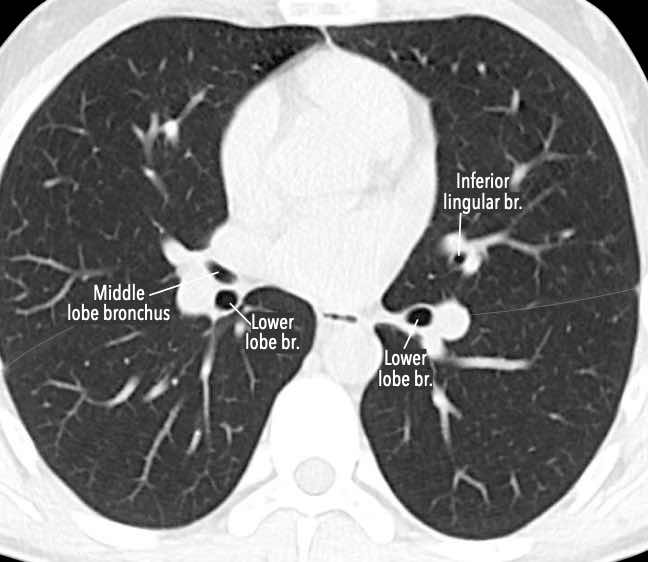

Phế quản trên CT

Cuộn qua các hình ảnh để quan sát khí quản phân chia thành phế quản chính phải và trái, sau đó tiếp tục phân chia thành các phế quản thùy và phế quản phân thùy.